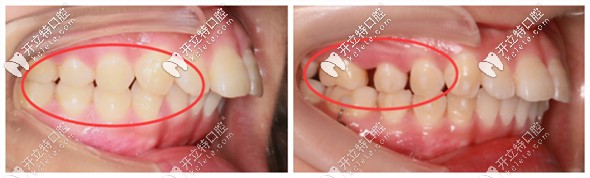

<真人案例展示>? ? ?↓隱適美磨牙后推的矯正案例圖

在正畸中,所謂的推磨牙向后,就是將口內(nèi)的磨牙依次往后移動,來給前牙區(qū)的牙齒獲得內(nèi)收和排列的空間。

把磨牙往后推,是隱適美矯正器的強(qiáng)項(xiàng),通常每一側(cè)可以推出4-5個(gè)毫米的間隙,有醫(yī)生推出了十毫米(這點(diǎn)因人而異,根據(jù)個(gè)人軟組織情況,避免過量遠(yuǎn)移引起冠周炎)。